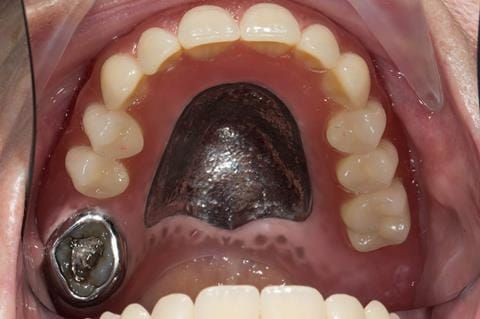

- Poorly fitting cobalt chromium based maxillary partial denture, which has been added to. This exhibited poor retention, stability and tissue fit (support). Unable to wear a new acrylic based denture.

Following consultation and second discussion appointment the patient chose to have option 2 namely, a window denture - maxillary cobalt chromium based partial denture. The clinical situation and treatment process is shown in detail below with photographs. The patient was successfully rehabilitated with this and her quality of life considerably improved. The clinical work was provided by Finlay and the technical work by Rowan.